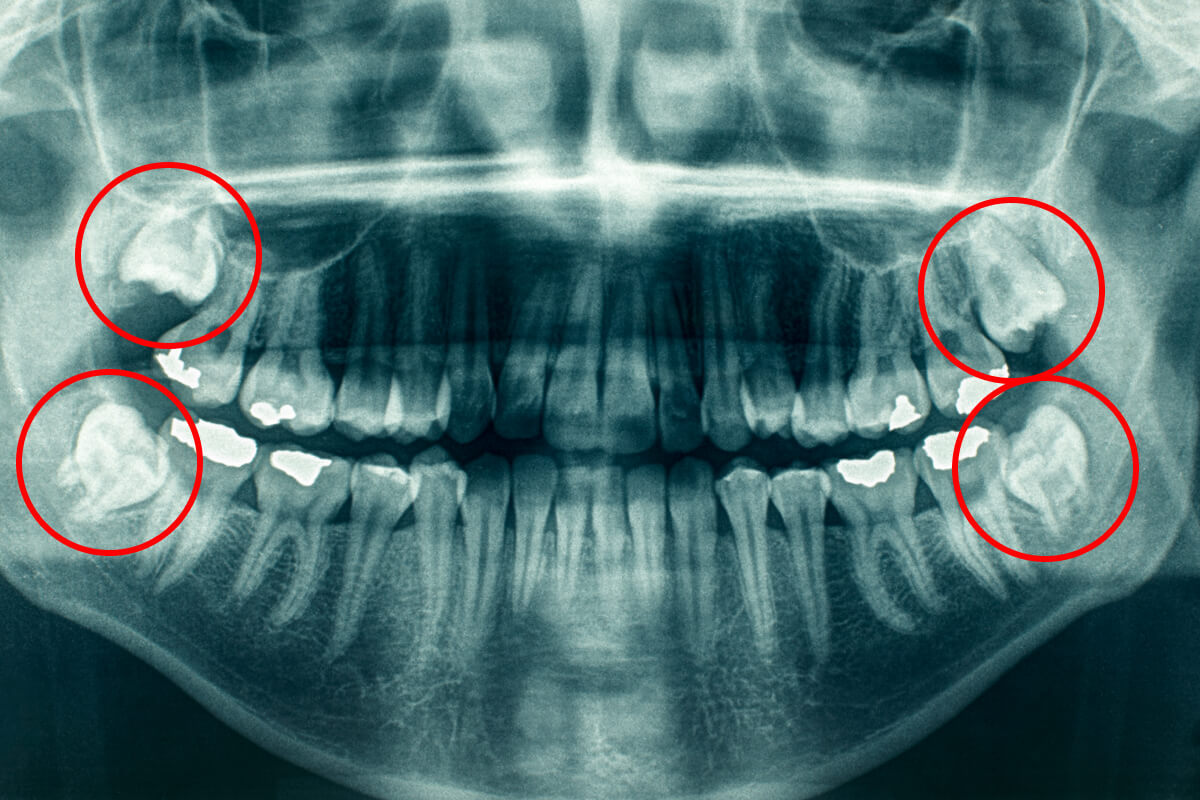

Mnoho pacientov má z pojmu „chirurgický zákrok“ obavy. U nás sú však zbytočné. Základom úspechu je špičková diagnostika. Pred každým zákrokom urobíme digitálny RTG snímok (prípadne 3D CT vyšetrenie), vďaka ktorému stomatochirurg presne vidí polohu koreňov a nervov.

1. Plánovanie: Na základe snímky lekár zvolí najšetrnejšiu cestu k zubu.